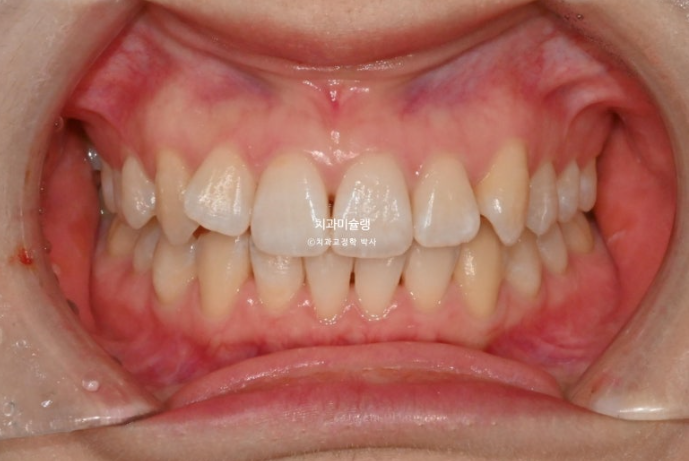

작년 1월, 앞니 덧니 교정을 위해 온 환자분입니다. 튀어나온 측절치 이외에는 신경쓰이는 부분은 없다고 하셨죠.

정면사진에서 블랙트라이앵글, 중심선 불일치 등이 보입니다.

덧니쪽으로 중심선은 치우치기 마련이지만 그 이외에도 양쪽 어금니 교합관계가 다르다 보니 중심선 불일치가 크게 나타납니다.